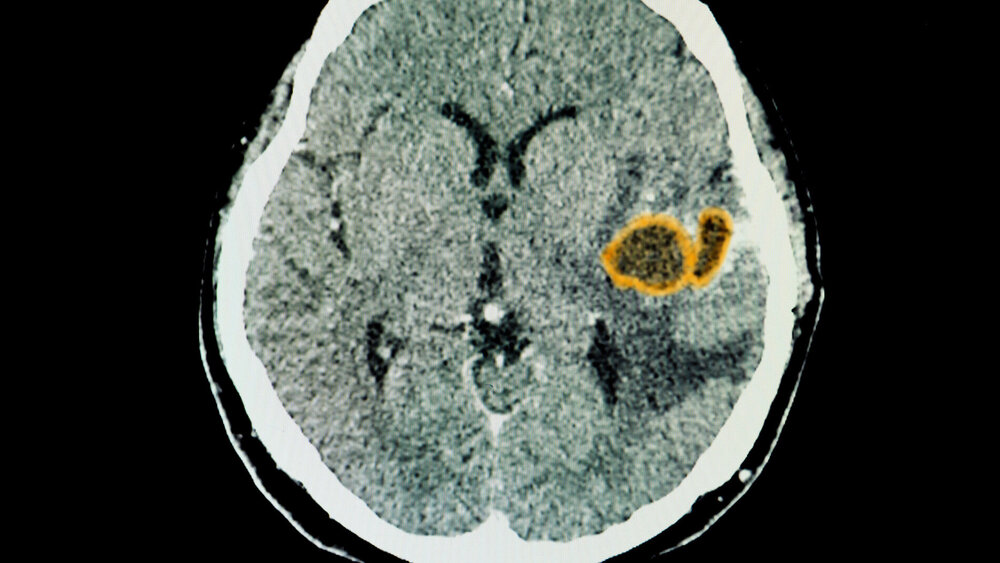

Sind orale Bakterien unterschätzte Verursacher von Hirnabszessen?

Eine Studie der Universität Plymouth und dem University Hospitals Plymouth NHS Trust zeigt, dass orale Bakterien auch dazu beitragen können, dass Patienten potenziell lebensbedrohliche Abszesse im Gehirn entwickeln. Intrazerebrale Abszesse sind zwar relativ selten, gehen aber mit einer hohen Mortalität und Morbidität einher.